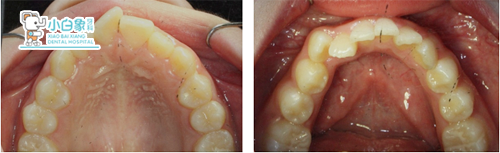

QQ截图20180120141917.png

治疗前

QQ截图20180120141922.png

治疗后

治疗前后对比

QQ截图20180120141933.png

QQ截图20180120141938.png